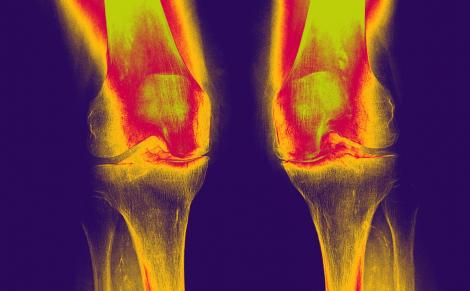

Dans un essai clinique, le sulfate de chondroïtine s'est avéré aussi efficace que le célécoxib pour réduire la douleur et améliorer le handicap fonctionnel des patients atteints d’arthrose du genou.

Au total, 604 patients atteints de gonarthrose ont été inclus dans 16 centres en Belgique, République tchèque, Italie, Pologne et Suisse. Les participants ont pris soit du sulfate de chondroïtine (800 mg/jour), soit du célécoxib (200 mg/jour), soit un placebo. Au final, le sulfate de chondroïtine s’est avéré aussi efficace que le célécoxib pour réduire la douleur et améliorer le handicap fonctionnel des patients atteints d’arthrose du genou. « Le traitement de choix de l’arthrose fait toujours l’objet d’une grande controverse. Les analgésiques et les anti-inflammatoires sont couramment utilisés mais ils sont de plus en plus associés à des risques de toxicité. Cet essai a prouvé de façon statistiquement significative que le sulfate de chondroïtine de qualité pharmaceutique est une option sûre et efficace pour le traitement à long terme des patients atteints d’arthrose du genou », avance le Dr Tomasz Blicharski (Pologne), investigateur de l’étude.